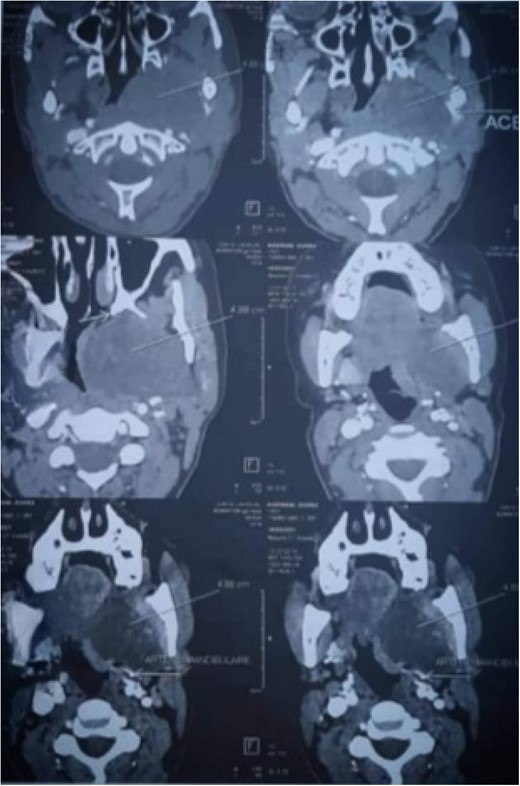

CT-scan has shown well-circumscribed, large-mass heterogenous areas of enhancement with size 6 × 44× 5 cm in the left parapharyngeal space displacing submandibular gland superiorly, carotid sheath anterolateral compressing the oropharyngeal airway (Fig. 1) Routine blood investigations were within the normal limit; hence, surgical removal under general anesthesia decision was done.